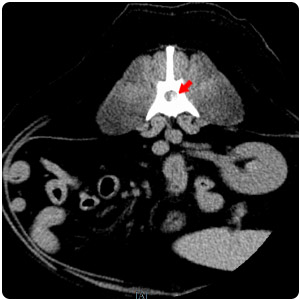

| 脊椎壓迫 transverse |

脊椎壓迫 sagittal |